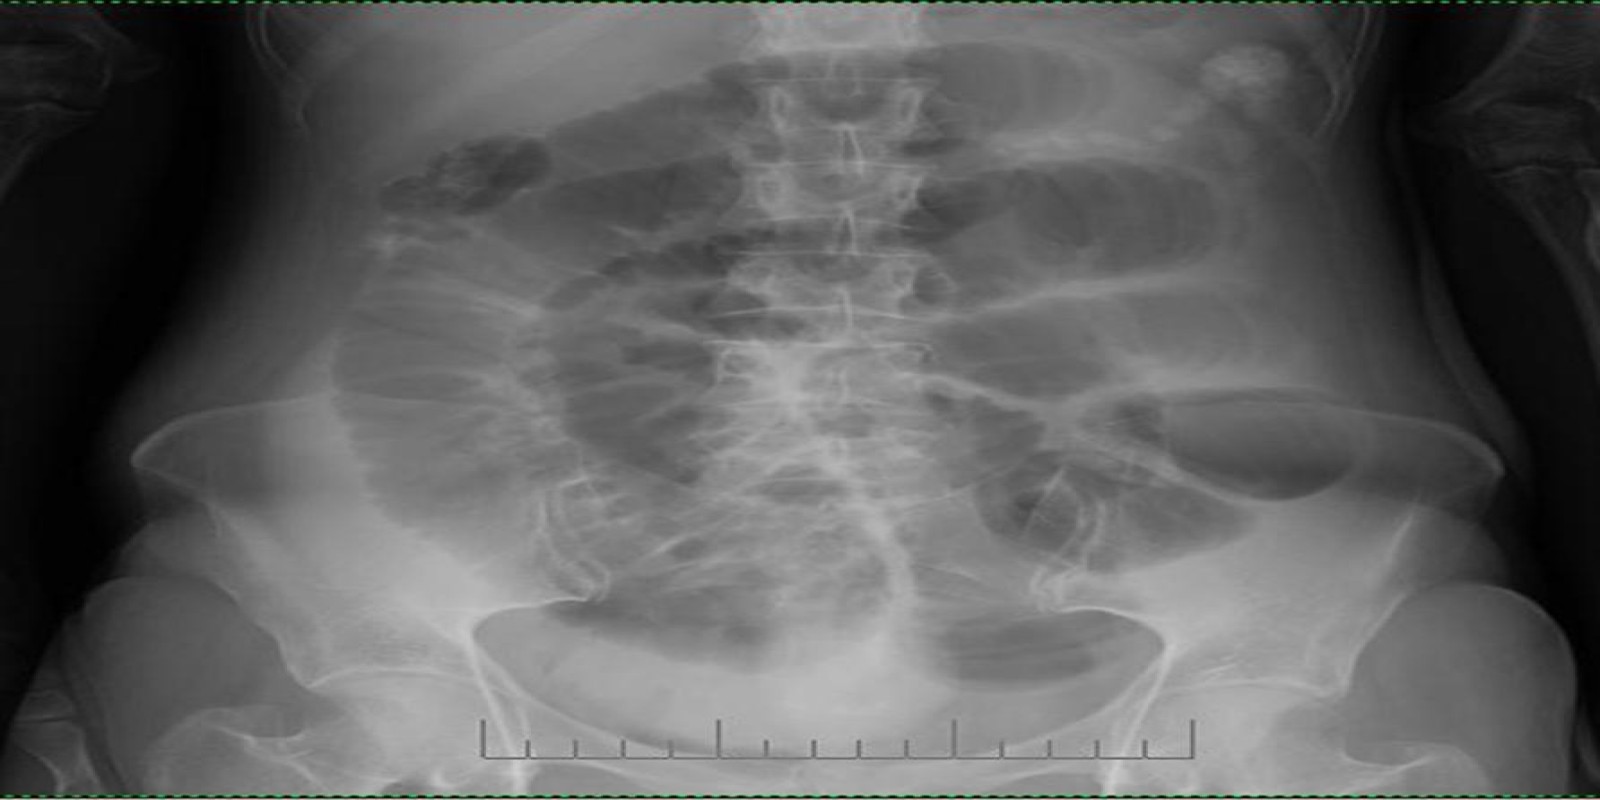

Caso Código 002C de Obstrução Intestinal do Delgado

Cod.: 002C